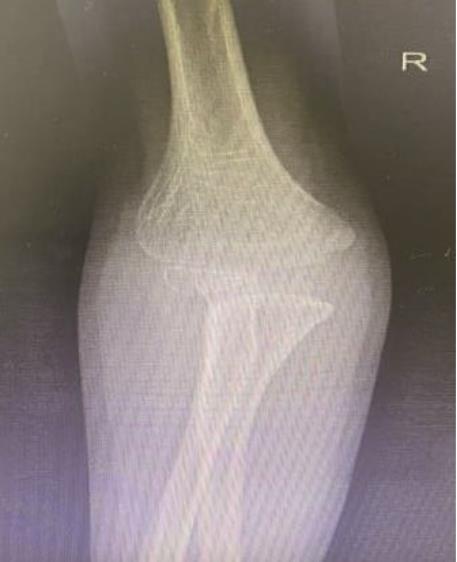

• 3D打印下精准截骨术治疗先天性尺桡关节脱位1例报道

摘要: